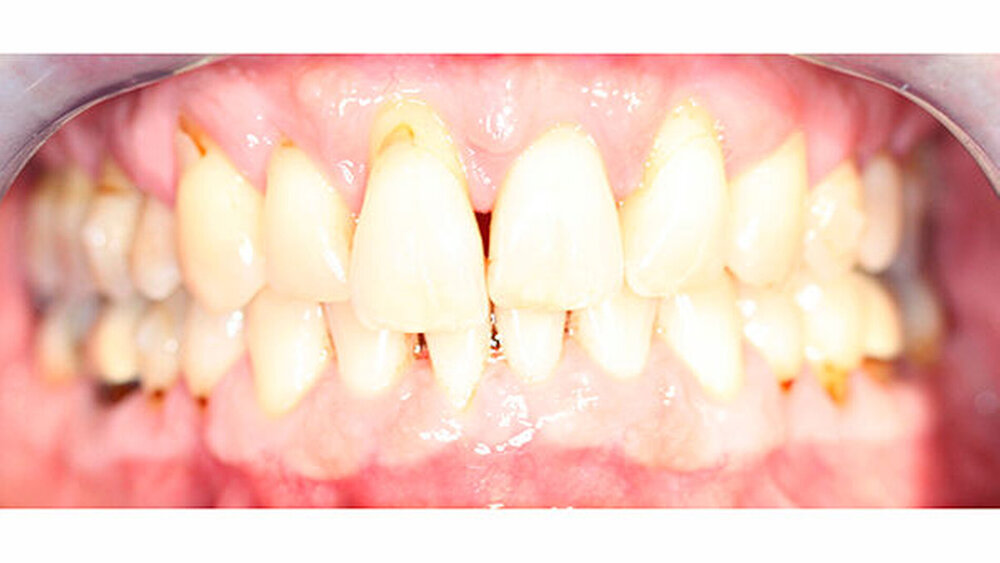

Eine Beurteilung der parodontalen Situation an Zahn 11 offenbarte mesial und distal Sondierungstiefen von jeweils 6 mm.

Röntgenologisch stellte sich im Orthopantomogramm der bereits intraoral ersichtliche horizontale und vertikale Knochenabbau mit Attachmentverlust an einzelnen Zähnen dar. Die Erhaltungswürdigkeit einzelner Zähne war aufgrund des starken Knochenverlustes beziehungsweise der Beeinträchtigung des Halteapparates als kritisch zu beurteilen.

Zudem wurde die Diagnose einer Parodontitis gestellt, die eine Rücküberweisung an den Hauszahnarzt erforderlich machte (Abbildung 2).